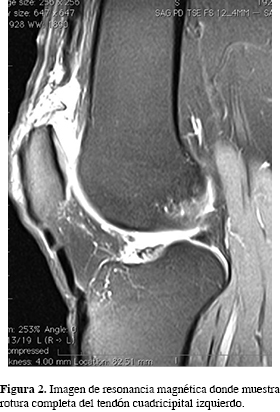

El estudio mediante resonancia magnética mostró una evidencia objetiva de discontinuidad de fibras tendinosas de forma completa en el tendón cuadricipital izquierdo, con una discontinuidad casi completa en el lado derecho (Figuras 1 y 2).

El diagnóstico fue de rotura completa del tendón cuadricipital en la rodilla izquierda y de parcial (más de 80% de las fibras) en la derecha.